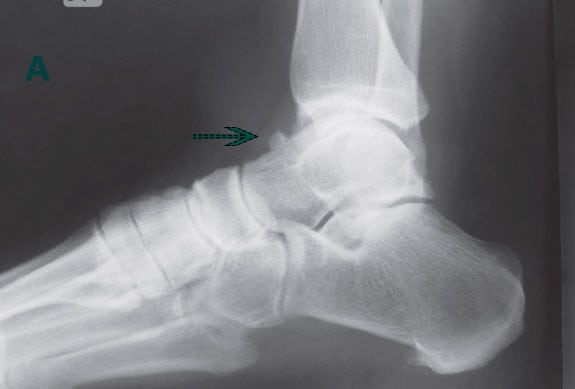

Хруст и щелчки в голеностопных суставах обычно возникают после 50 лет из-за снижения выработки в организме коллагена и эластина, ухудшения кровообращения, замедления регенерации хрящевых тканей. У молодых людей эти звуки появляются редко: обычно после спортивных травм, интенсивных тренировок, тяжелой физической работы. Причины потрескивания суставов во время ходьбы бывают естественными и патологическими. Дифференцировать их самостоятельно в домашних условиях невозможно. После обращения к врачу проводится ряд инструментальных исследований, из которых наиболее информативна рентгенография. Лабораторная диагностика показана при одновременном возникновении хруста, отечности и болезненных ощущений.

- тендинита, тендовагинита — воспаления сухожилия и (или) его оболочки в месте прикрепления к кости;

- деформирующих артрозов, спровоцированных разрушением гиалиновых хрящей, сопровождающихся формированием костных наростов — остеофитов;